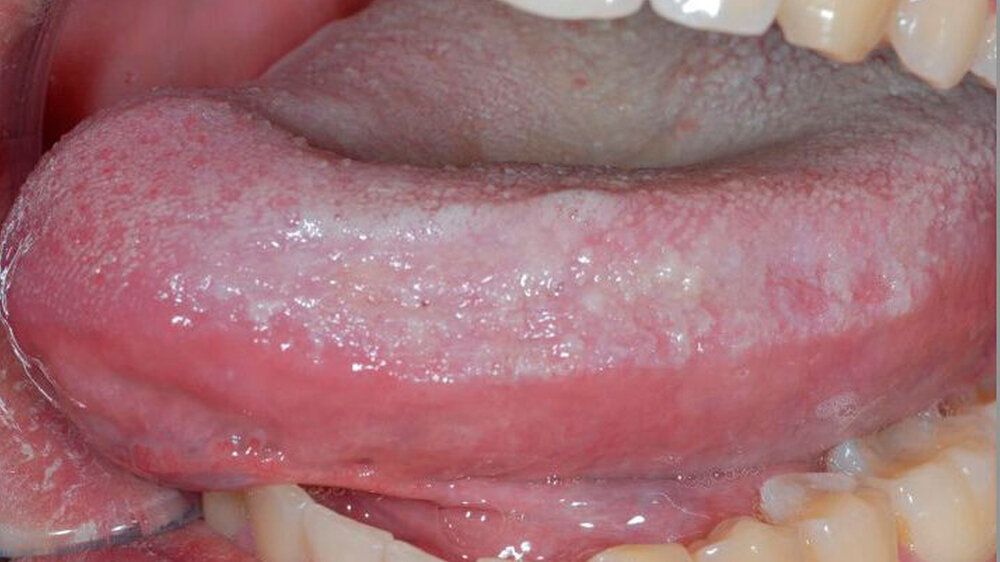

Die PREDICT-OLP-Studie stellt eine prospektive, multizentrische und interdisziplinäre Untersuchung zur Prädiktion der malignen Entartungstendenz von weißlichen, nicht wegwischbaren Mundschleimhautveränderungen dar. Ziel der Studie ist die Evaluation des Melanoma-associated-Antigens A (MAGE-A) sowie weiterer immunologischer Marker als objektive Parameter in der Risikoeinschätzung potentieller Präkanzerosen der Mundschleimhaut.

In retrospektiven Studien konnte die Assoziation zwischen der MAGE-A-Expression oraler Leukoplakien und deren maligner Entartung bereits mit sehr hoher Sensitivität und Spezifität nachgewiesen werden. Nun sollen diese Erkenntnisse in einem prospektiven Studiendesign an einem großen Patientenkollektiv bestätigt werden.

Aktuell besteht der diagnostische Goldstandard aus dem histologisch bestimmten Dysplasiegrad der Mundschleimhautläsion. Dieses Verfahren ist jedoch sehr subjektiv und mit Hinblick auf die Risikoeinschätzung der Krebsentstehung nur eingeschränkt aussagekräftig.

Mit der MAGE-A-Expression möchten wir die aktuell übliche Diagnostik von Mundschleimhautveränderungen um ein objektives Standbein erweitern um zukünftig Leukoplakien mit hohem Risiko für die Entstehung eines Mundhöhlenkarzinoms frühzeitiger und sicherer erkennen zu können.